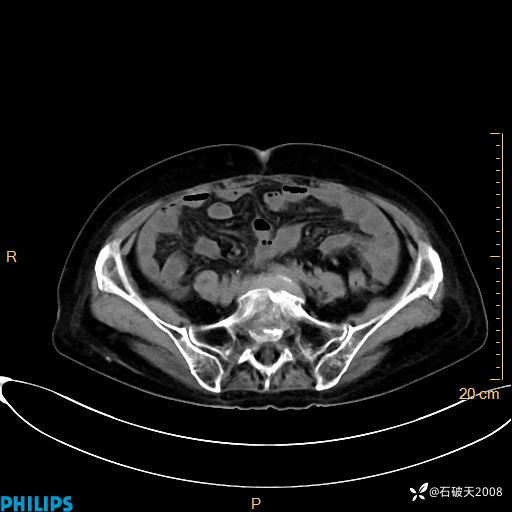

动脉期